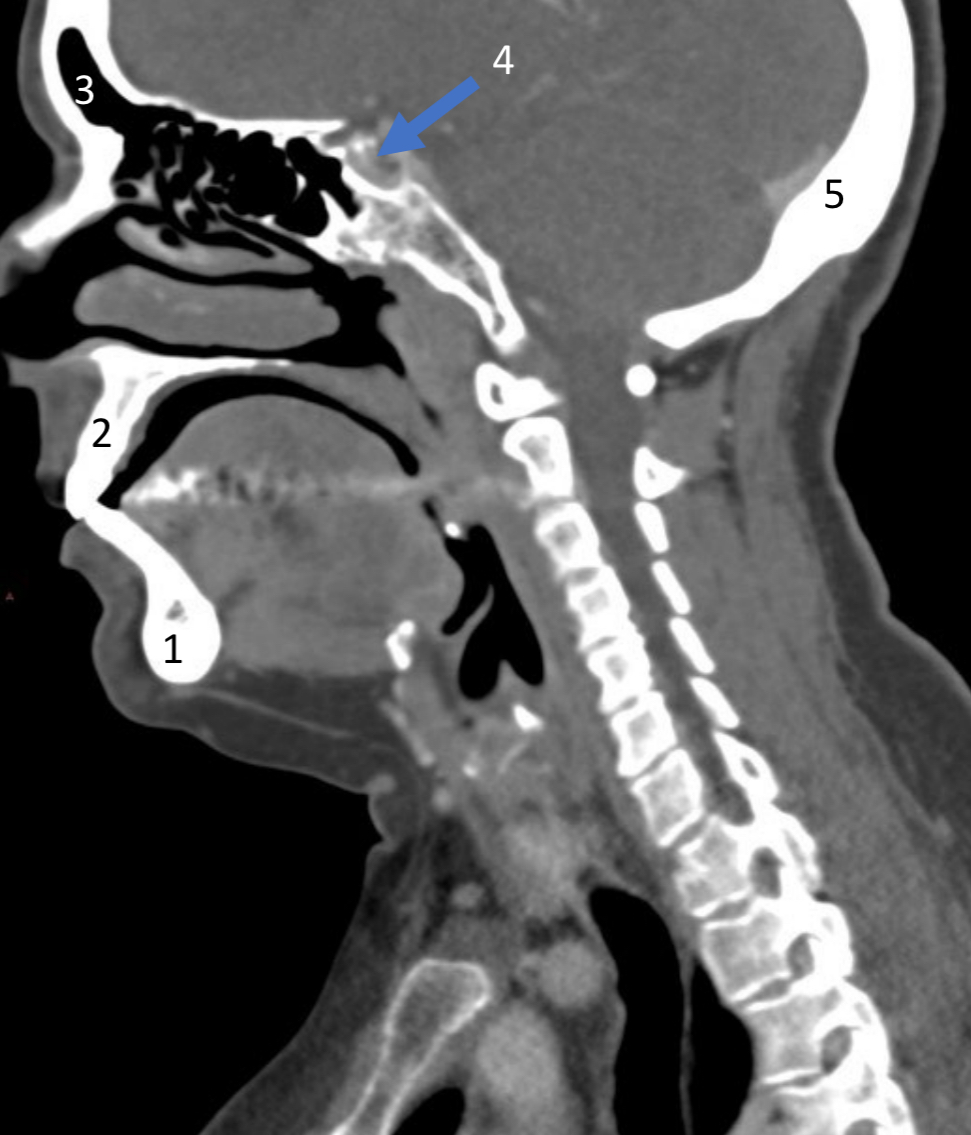

Mandible

ID bone

Maxilla

ID bone

Frontal sinus

ID structure

Pituitary fossa

ID structure

Occipital

ID bone

Lambdoid suture

ID structure

Frontal sinus

ID structure

Orbital margin

Orbit

Maxillary sinus

ID structure

Mandibular condyle

ID structure

Inferior nasal concha

ID structure

Hard palate

ID strucutre

Gonial angle

ID strucutre

Petrous ridge

ID structure

Groove of middle meningeal a.

ID structure

Roof of orbit

ID structure

Frontal sinus

ID structure

Pituitary fossa

ID structure

Petrous ridge

ID structure

Sphenoid sinus

ID structure

Hard palate

ID structure

Mastoid air cells

ID structure

Zygomatic arch

ID structure

Mandibular condyle

ID structure

External auditory meatus

ID structure

Mastoid air cells

ID structure

Foramen magnum

ID structure

Foramen ovale

ID structure

Foramen spinosum

ID structure